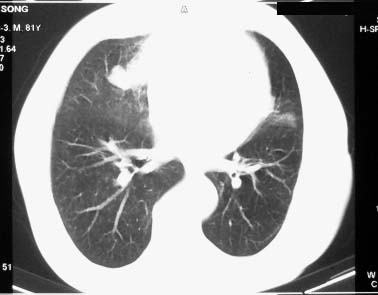

右肺上叶肿块,其远侧段肺组织炎性渗出性改变,局部胸膜粘连,肺门侧边缘光滑锐利,可见结节样病灶;右肺尖纤维索条状影,局部肺纹理纠集,纵隔窗窗宽不合适,病灶内部情况显示不清,未见明显淋巴结肿大及钙化.

考虑:1.右肺上叶周围性肺癌并肺内转移;2.右肺尖陈旧性结核.3.左肺炎性病灶.

右肺中叶软组织块(挑剔一下纵隔窗窗宽不理想),其周围可见多个类圆形结节,右肺上叶尖段见斑片、索条状致影,左肺小结节。

1.右肺周围型肺癌伴肺内转移;

2.右肺上叶陈旧性结核;

3.左肺炎性结节;